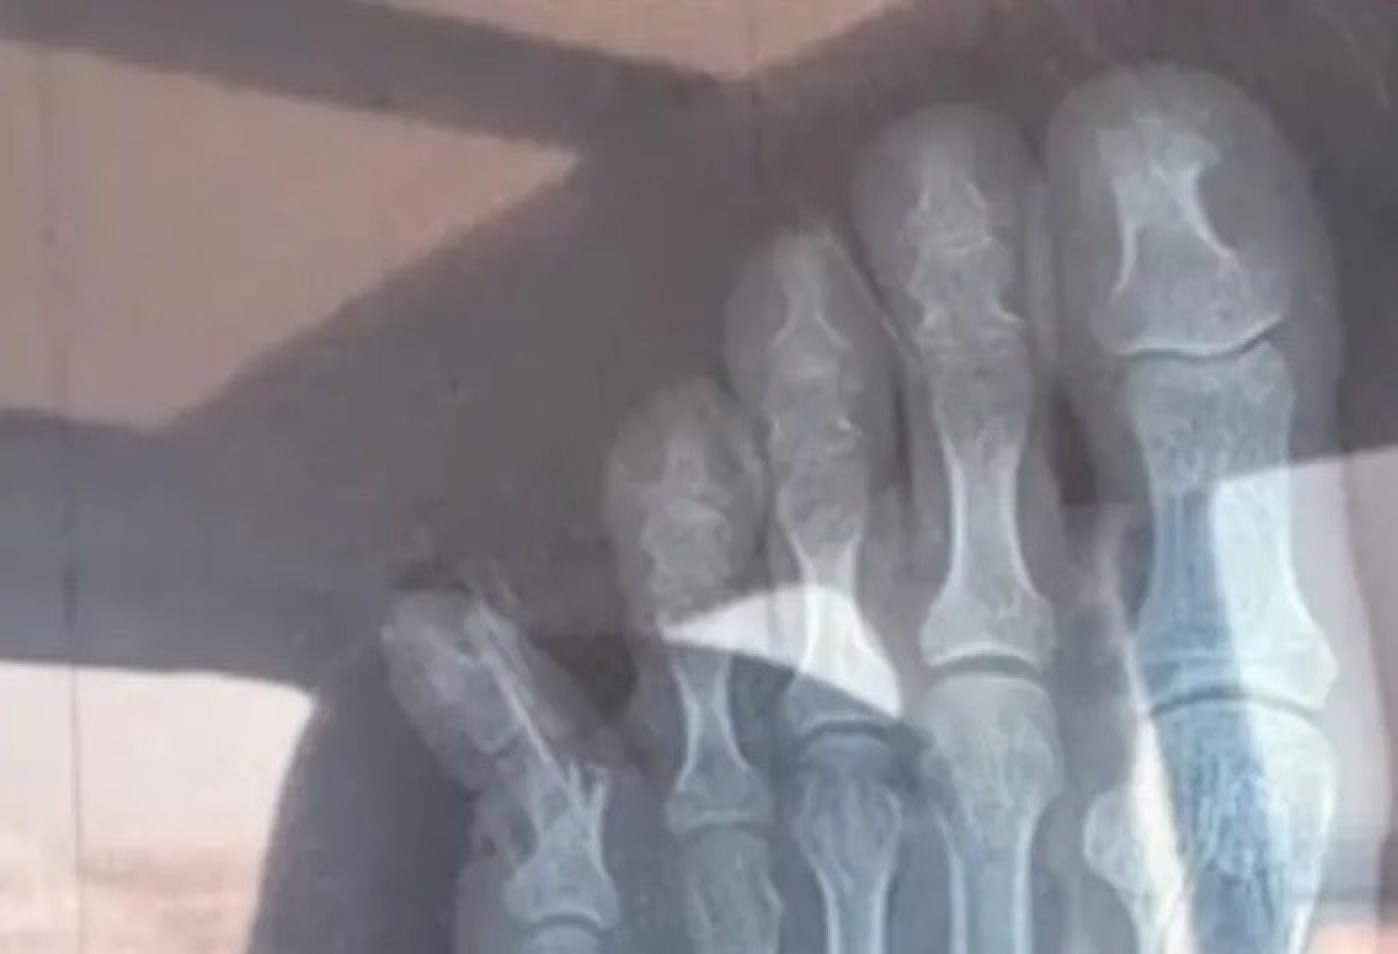

Theo SCMP, hình ảnh được chia sẻ trên mạng cho thấy ngón chân út bên phải của chị Trương hướng hẳn ra ngoài, gần như tạo thành góc 45 độ.

Kết quả chụp X-quang xác nhậnngười phụ nữ bị gãy xương và đang trong quá trình kiểm tra và điều trị tại bệnh viện. Cô phải băng bó cả bàn chân. Sau khi sự việc xảy ra, chị Trương đã đăng ký cho con trai vào một lớp học thêm sau giờ chính khóa.